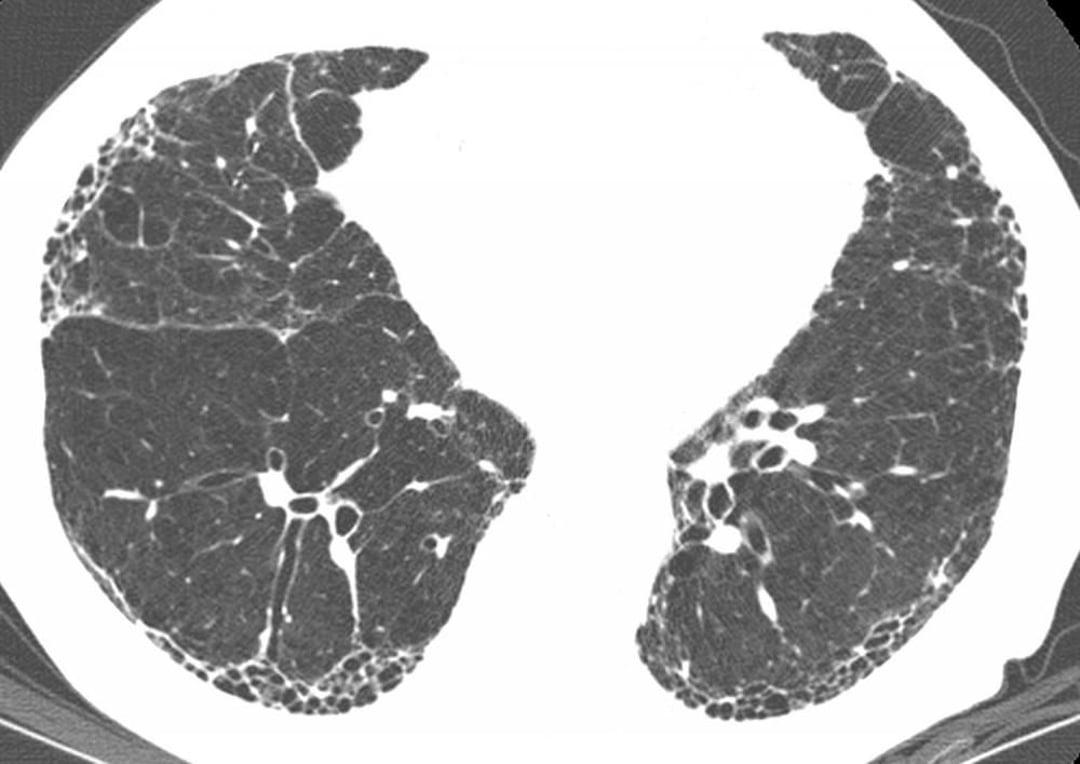

肺里的 “海绵” 变硬后还突然 “闹罢工”?肺纤维化一旦加重,就像呼吸路上的 “急刹车”,但这可不是 “绝症警报”!作为呼吸科医生,今天用大白话教你科学应对。 先认清 “加重信号”:1 个月内突然喘得更凶,平地走路都气短;干咳变频繁,甚至憋得睡不着;血氧仪读数常低于 93%(正常≥95%)。这时候别硬扛,赶紧就医 ——HRCT 会发现肺部在原有 “网格” 基础上,冒出新的 “磨玻璃影”,这就是病情加重的明确证据。 应对分三步走:第一步 “紧急就医”,直奔呼吸科或急诊科,记得带既往 CT 报告和用药记录,方便医生快速对比;第二步 “规范治疗”,住院后会先吸氧纠正缺氧,再用激素冲击控制急性炎症,配合抗纤维化药物延缓进展;第三步 “排查诱因”,感染、胃食管反流误吸、空气污染都是常见 “导火索”,针对性处理才能避免复发。 预防比治疗更关键:每年打流感和肺炎疫苗,减少感染风险;戒烟 + 远离粉尘、油烟,给肺部 “减负担”;睡前 3 小时别吃东西,防胃酸反流呛到肺里;平时练太极拳、八段锦,提升肺功能储备。 记住:肺纤维化加重是 “提醒信号”,不是 “终点通知”。早干预、找对诱因、坚持规范治疗,就能让 “变硬的海绵” 少添新伤,守护呼吸主动权。